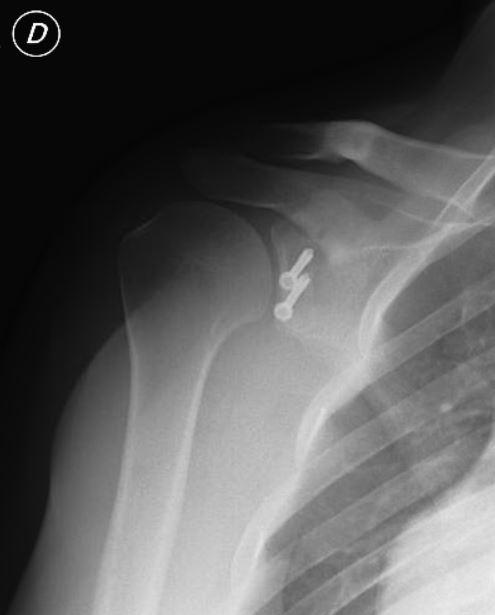

Questo intervento consiste in una incisione anteriore alla spalla di circa 6-7 cm per accedere all’articolazione. Si effettua in questo caso l’intervento di Latarjet cioè si trasferisce la coracoide (frammento della scapola) sul bordo anteriore della glena e si fissa con due viti in modo da aumentare lo spazio su cui la testa omerale può ruotare senza uscire nuovamente. Questa procedura è particolarmente indicata nei casi di grave deficit ossei e applicata con successo in molti sportivi che praticano sport da contatto come i rugbisti.